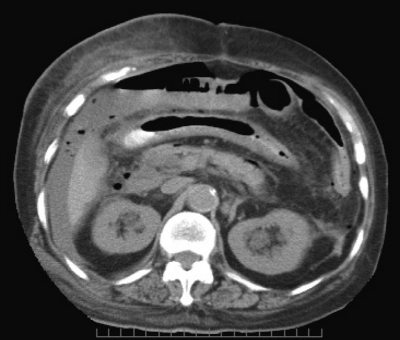

血液所見:赤血球 320 万、Hb 10.7 g/dL、Ht 30 %、白血球 15,300、血小板 18 万。血液生化学所見:総蛋白 6.6 g/dL、アルブミン 3.4 g/dL、総ビリルビン 0.6 mg/dL、AST 50 U/L、ALT 62 U/L、LD 330 U/L (基準 176〜353)、ALP 270 U/L (基準 115〜359)、γ-GTP 63 U/L(基準 8〜50)、アミラーゼ 140 U/L(基準 37〜160)、CK 110 U/L(基準 30〜140)、尿素窒素 28 mg/dL、クレアチニン 1.0 mg/dL、尿酸 6.0 mg/dL、血糖 130 mg/dL、HbA1c 5.0 %(基準 4.6〜6.2)、総コレステロール 178 mg/dL、トリグリセリド 190 mg/dL、Na 142 mEq/L、K 4.2 mEq/L、Cl 98 mEq/L。CRP 11 mg/dL。腹部 CTを別に示す。

適切な対応はどれか。

e. 孔部切除閉鎖+人工肛門造設術<Hartmann 手術>